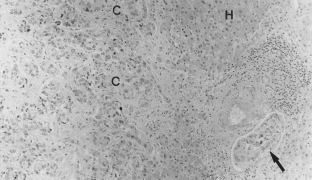

Fig. 2.